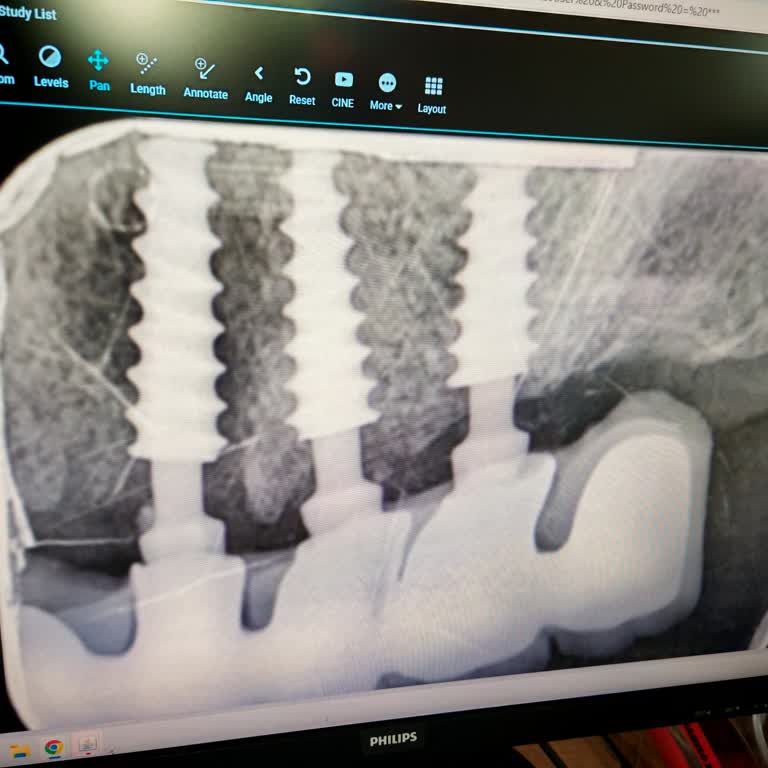

Yaklaşık bir buçuk ay önce annemle birlikte Bahçeşehir Avrupa Diş kliniğine muayene ve tedavi planı için gittik. Röntgenler çekildi, dişlerimize bakıldı ve hangi işlemlerin yapılacağı bize detaylı şekilde anlatıldı. Bu görüşmeler sonunda annemin tedavisi için 45.000 TL, benim tedavim için ise 43.000...